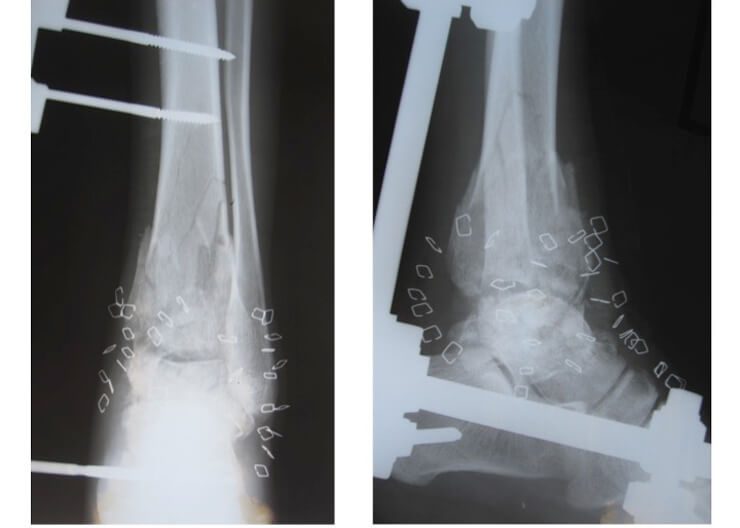

A 17-year-old adolescent sustained a GSW to his right distal leg (medial entrance wound, lateral exit wound) (Figure 7). He had a Gustilo IIIc [5,6] compound fracture (Figure 8). Acutely, the posterior tibial artery was ligated, tissues debrided and an external fixator placed. Two further soft tissue debridements were performed and unfortunately, the medial wound was closed. There was total loss of function in the peroneal and posterior tibial nerves.

Figure 8: X-ray right leg: Gustilo IIIc comminuted, compound fracture

of distal third tibia and fibula with bone gap.